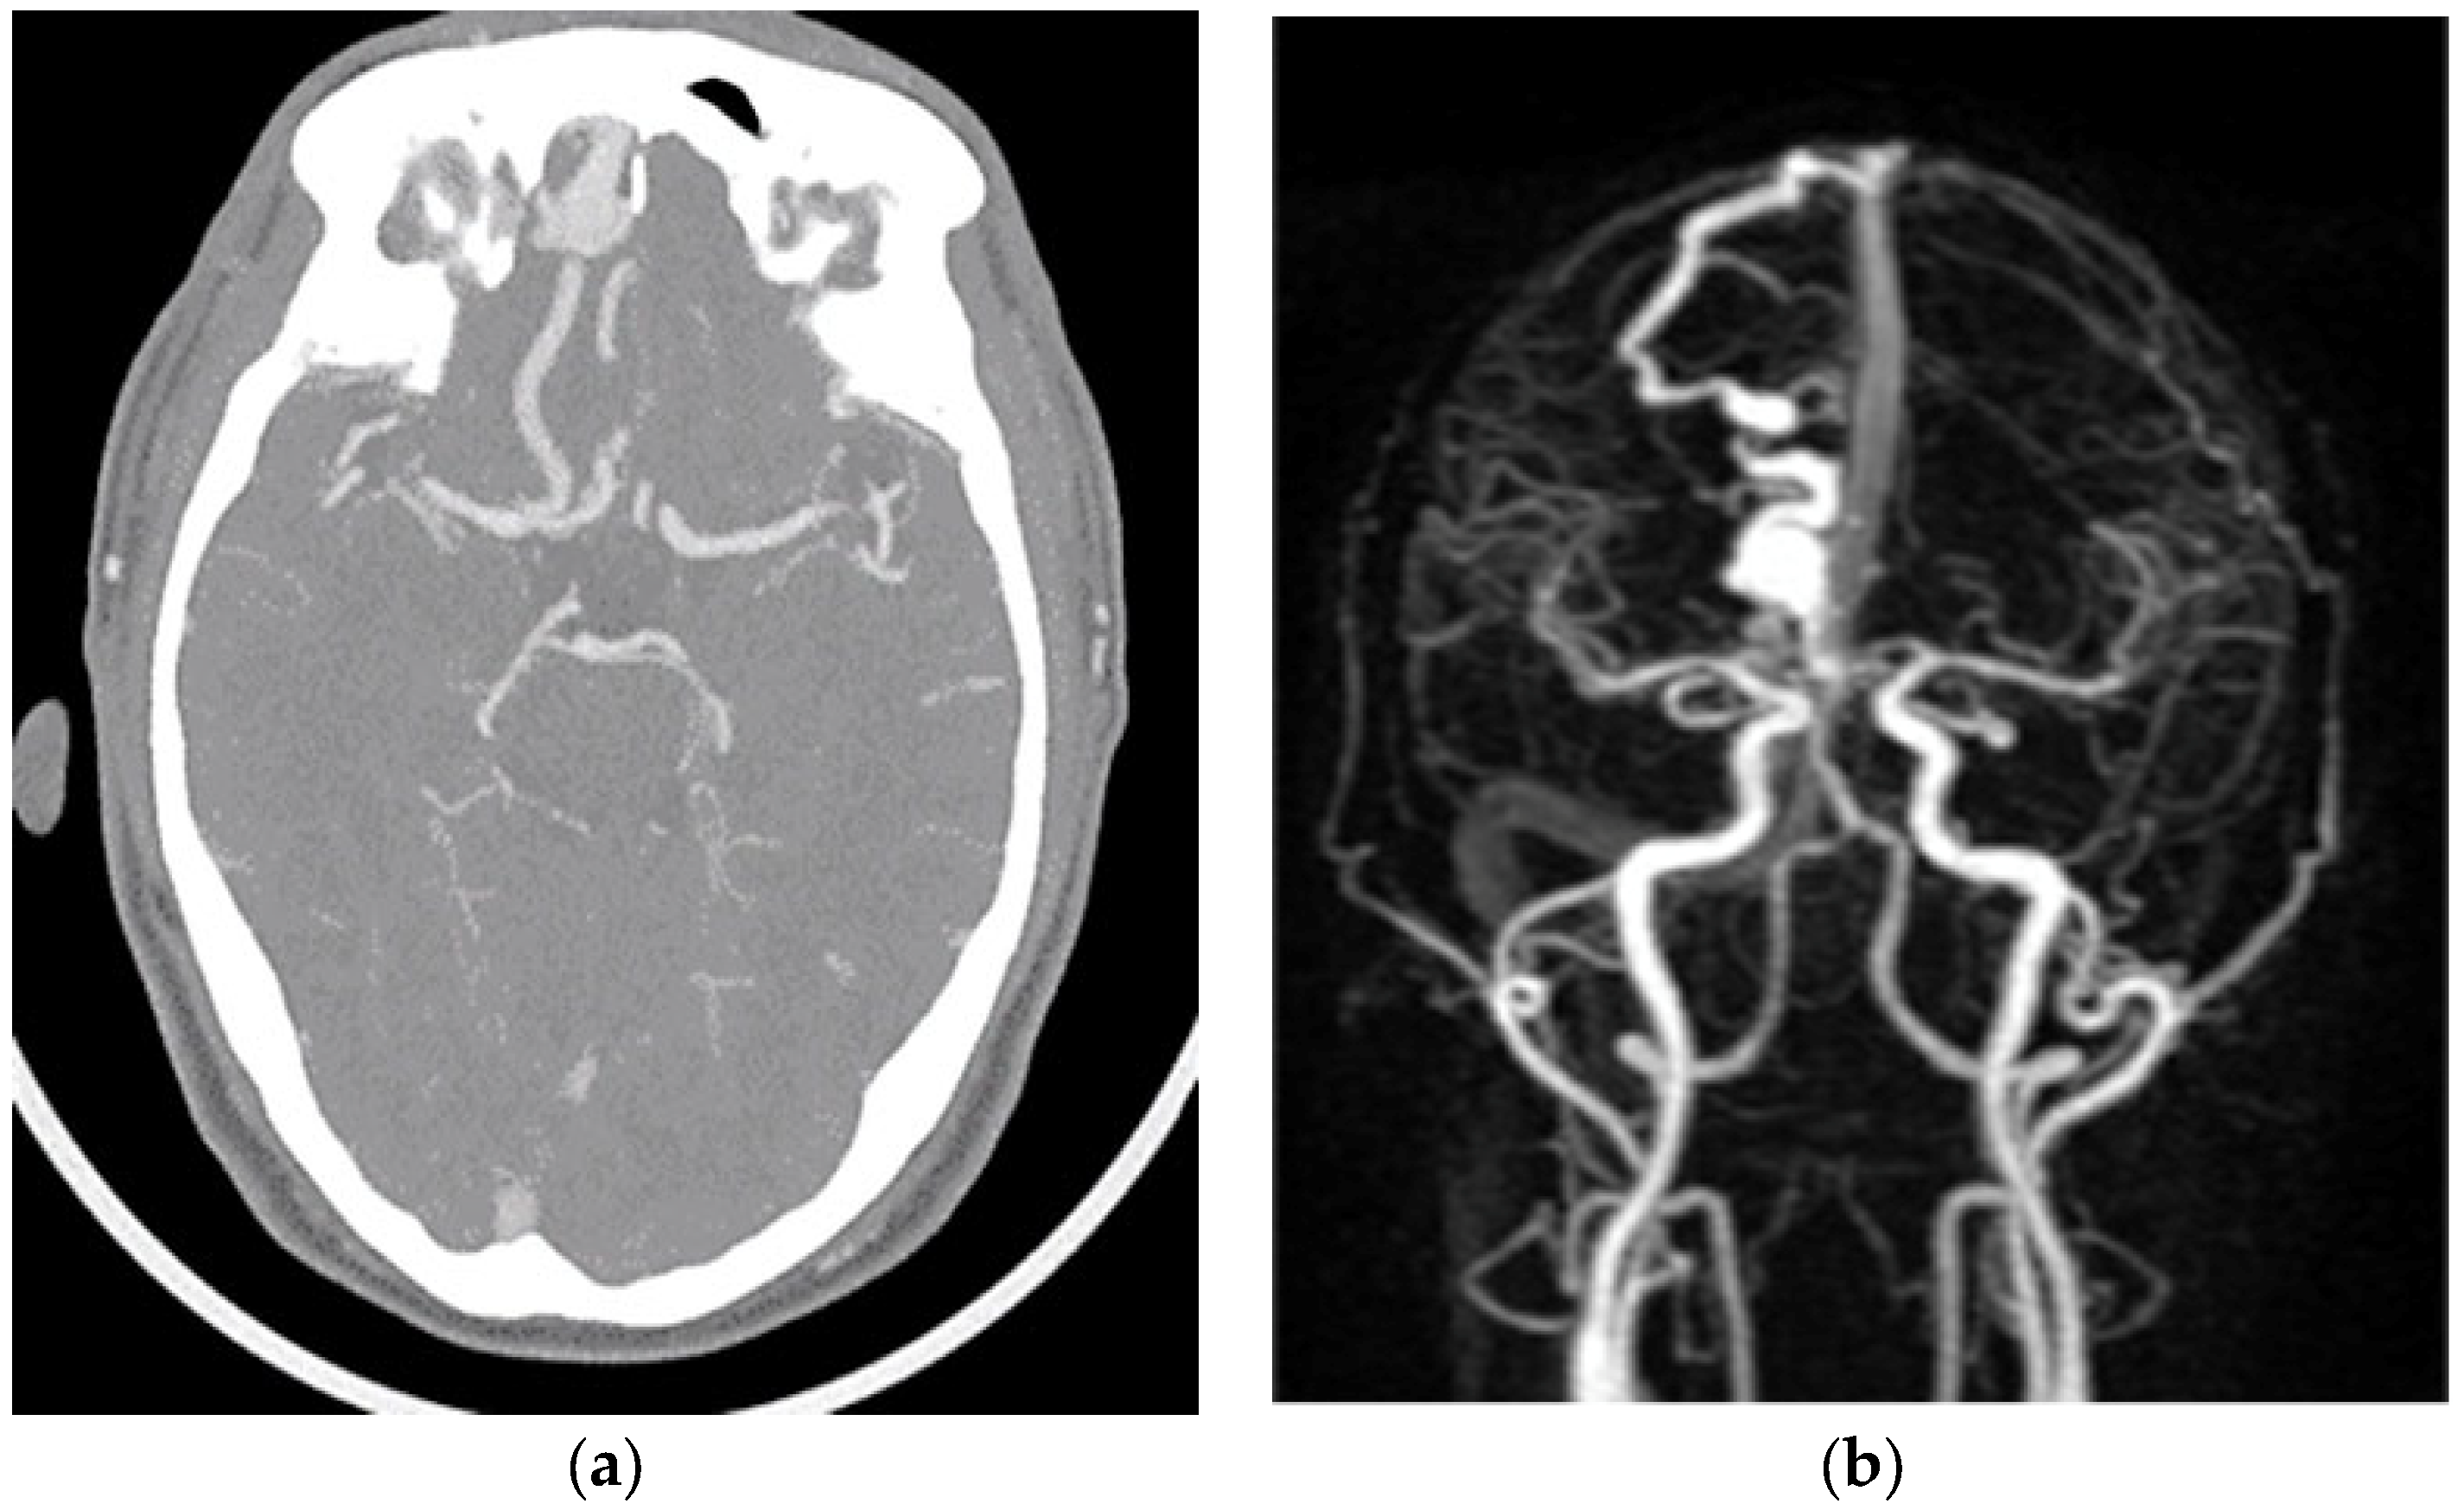

2. Case Report